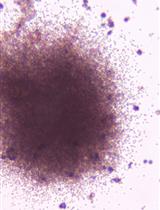

Human embryonic stem cells (hESCs) Undifferentiated hESCs were cultured on irradiated mouse embryonic fibroblast (MEF) feeders in DMEM/F12 medium supplemented with 20% KnockOut serum replacement, 0.1 mM nonessential amino acids (NEAA), 1 mM GlutaMAXTM-1, 0.1 mM 2-mercaptoethanol (all from Invitrogen) and 8 ng/ml recombinant human FGF2 (Peprotech, catalog number: 100-18 B).